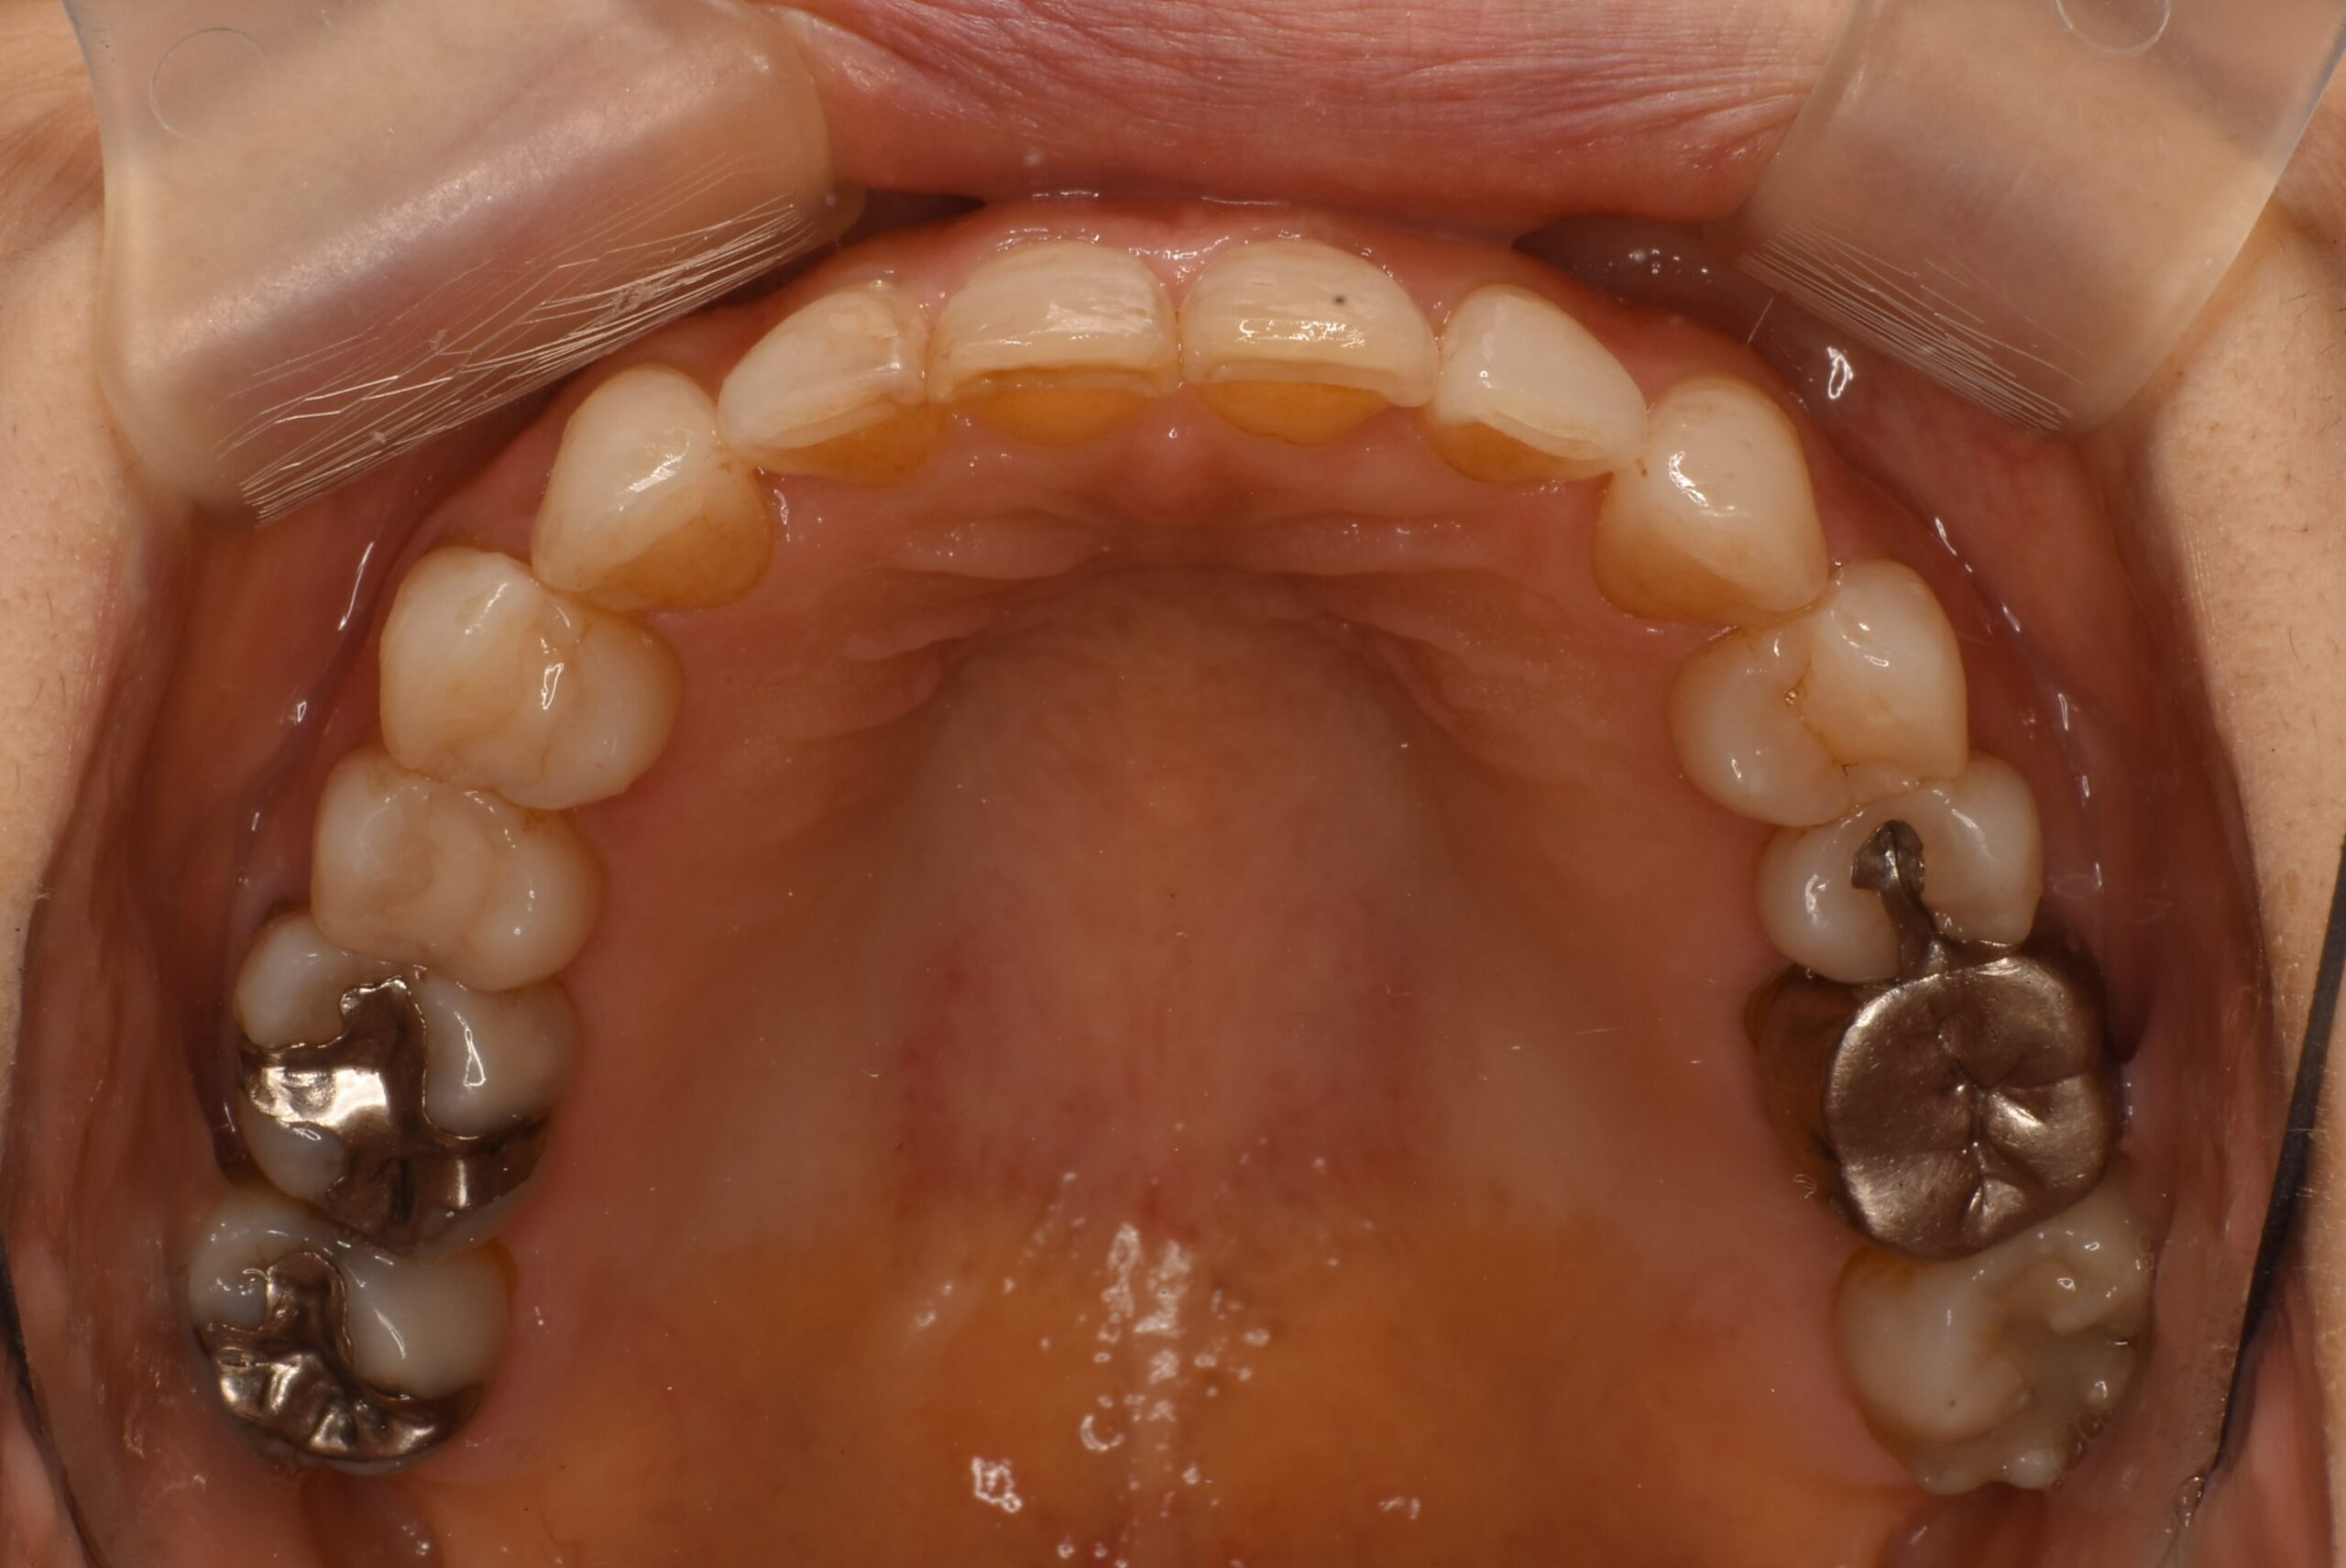

治療後上咬合面

| 治療内容 | 患者様は、上の前歯が1本だけ突出していることを気にされて来院された。口元の見た目にコンプレックスを感じており、人前で大きく笑うことに抵抗があるとのことであった。さらに、口が開きにくい・顎が鳴る・動かしづらいといった顎関節症の症状に加え、慢性的な首・肩のこりや頻繁な頭痛も訴えられていた。 目立たない矯正をご希望されたため、マウスピース型矯正装置「インビザライン」による治療を選択しました。前歯の1本だけが前方に突出していることに対し、全体の歯列バランスを考慮しながら、段階的に歯を移動させて整える治療。必要に応じて歯と歯の間のわずかな削合を行い、歯を並べるスペースを確保した。 |